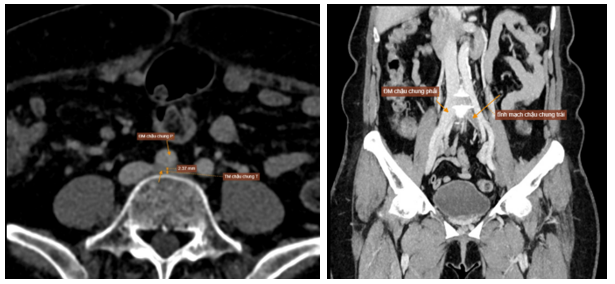

Hình 5: Hội chứng May – Thurner (tĩnh mạch chậu chung trái bị chèn ép bởi động mạch chậu chung phải và cột sống)

Xét nghiệm huyết học và sinh hóa trong giới hạn bình thường: WBC = 8,3k/uL, RBC = 5.1 M/uL, PLT = 233 k/uL, creatinin = 91,6 umol/L. Xét nghiệm đông cầm máu trong giới hạn bình thường với: PT = 13s (104%), aPTT = 26s , INR = 1. Do tình trạng huyết khối chỉ xảy ra ở chân trái, kèm bệnh nhân không có yếu tố nguy cơ gợi ý tăng đông, nên gợi ý nhiều đến hội chứng May – Thurner. Bệnh nhân được chụp CT tĩnh mạch chi dưới gợi ý đến hội chứng này. Kết quả CT như sau: tĩnh mạch chậu chung trái bị chèn ép bởi động mạch chậu chung phải và cột sống, đường kính tại gốc d # 2.3mm -> nghĩ hội chứng May – Thurner. Huyết khối cấp/ bán cấp gây tắc hoàn toàn hệ tĩnh mạch chậu trái. Huyết khối giai đoạn cấp/ bán cấp bán phần hệ tĩnh mạch đùi, khoeo và đoạn gần tĩnh mạch sâu cẳng chân trái. Huyết khối gần hoàn toàn tĩnh mạch cơ bụng chân trái. Huyết khối bán phần tĩnh mạch hiển bé.